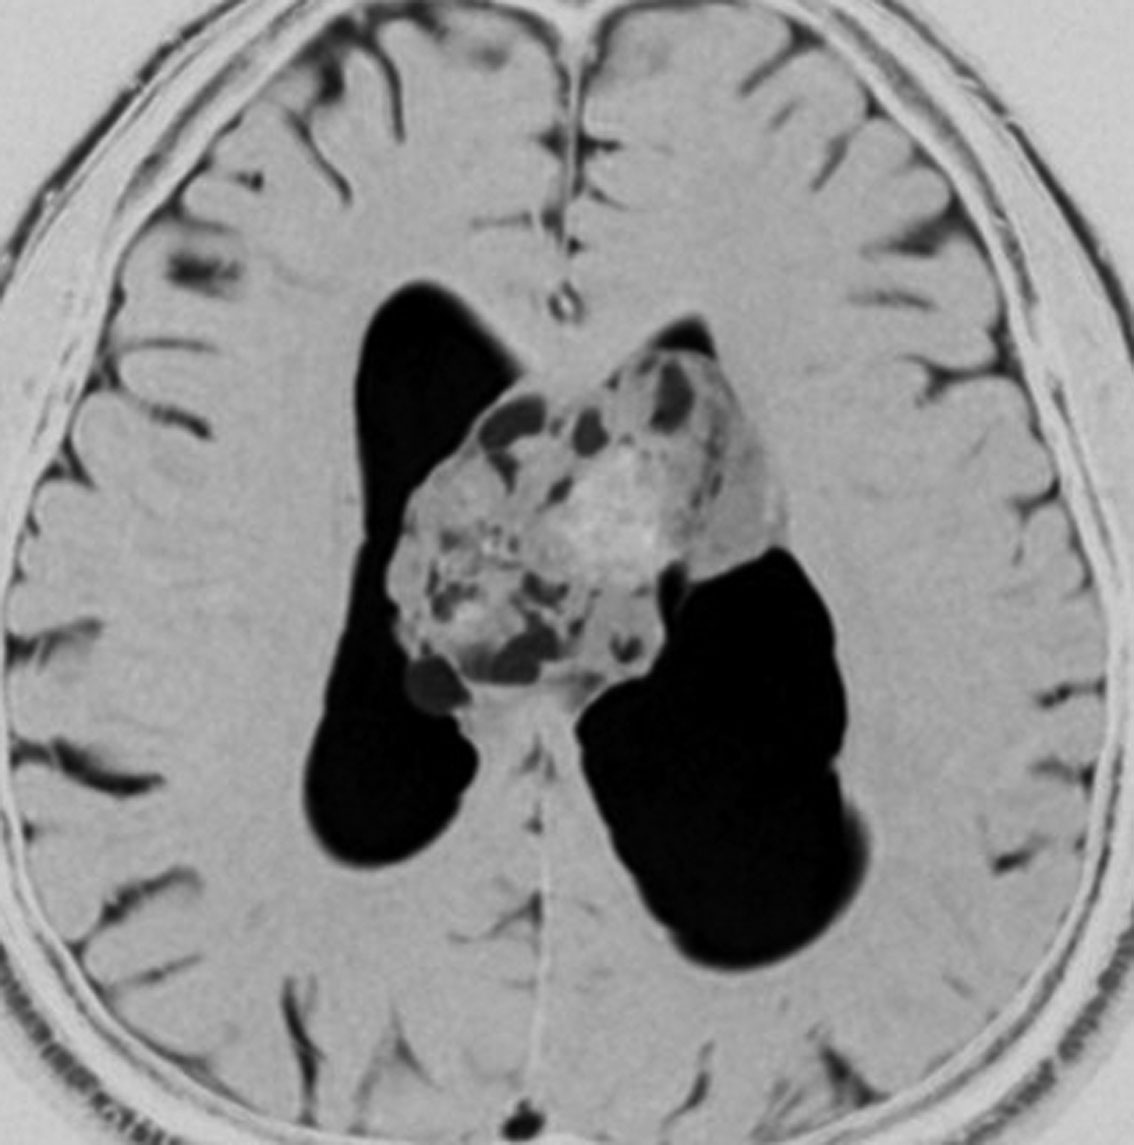

52歳の男性で,2008年に脳ドックで見つかって無症状でした。中枢性神経細胞種 central neurocytomaを疑いましたが,上衣下腫 subependymomaはまったく考慮に入れませんでした。壮年男性でしたから経過観察しました。右側は2019年,11年後のものです。徐々に増大して水頭症になり歩行障害がでてきました。

手術前の画像です。血管が豊富で大きな導出静脈がみられ,腫瘍内出血もあります。ガドリニウムでは部分的に増強されます。CISS/FIESTAの画像では,透明中核から発生したようにみえて,脳浸潤は全くありません。脳弓は腫瘍の底面にありますが,もちろん境界はっきりしません。これらもcentral neurocytomaの画像所見として捉えられるものです。

transcallosal approach 経脳梁法で亜然摘出しました。底面には脳弓があって剥離できないから全摘出はできません。病理所見は,のう胞形成を伴う線維性基質の中に楕円形の細胞が索状または小巣状に増生するものでsubependymomaと診断されました。異型は軽度で,核分裂像はなく,MIB-1染色率は1%以下のWHO grade Iの所見。EMAは細胞質にdot likeに陽性でしたがわずかであり,ependymomaとの合併腫瘍の診断には至りませんでした。

術後1年の画像です。無症状で復職できています。